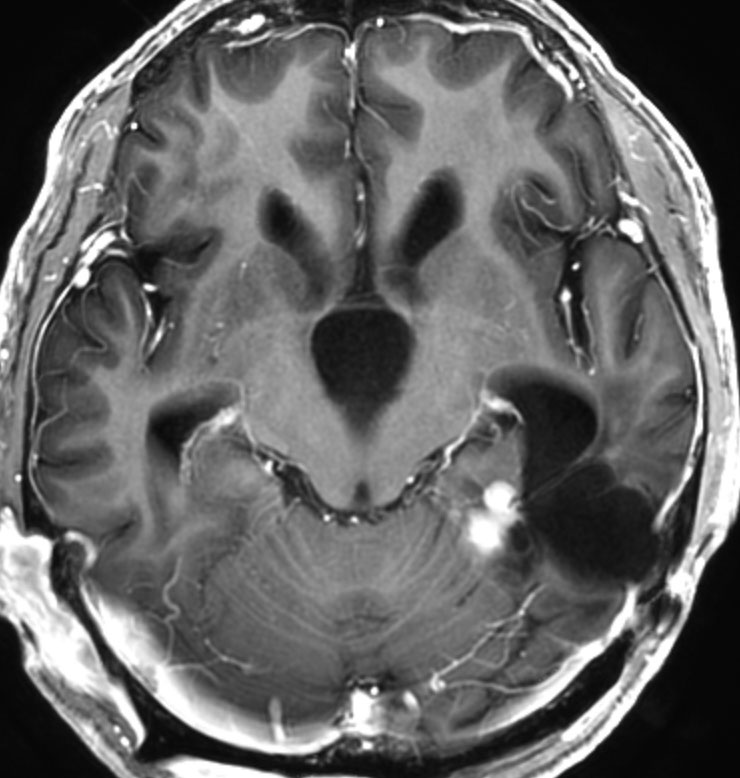

高齢者の無症候例です

60代の女性に無症候で発見された稀な部位のPXA。結節様ですが脳とのはっきりした境はなく,多房性ののう胞を伴っていました。T2とFLAIR像ではわずかな浸潤像あるいは腫瘍周辺浮腫が疑われます。PXAに特徴的な画像ですが,大脳深部発生でもあり,PXAと画像診断することはできません。定位脳生検術 MRI-guided sterotactic biopsyで病理組織診断を行ない経過観察しました。

3年観察したら嚢胞を伴って増大しました。幸いのう胞性拡大が脳表方向であったのでparietal transcortical approachで全摘出できました。側脳室三角部腫瘍への到達法と同じアプローチですが,この経路では頭頂葉症候を後遺することがありません。

術後は無症状で8年間再発はありません。